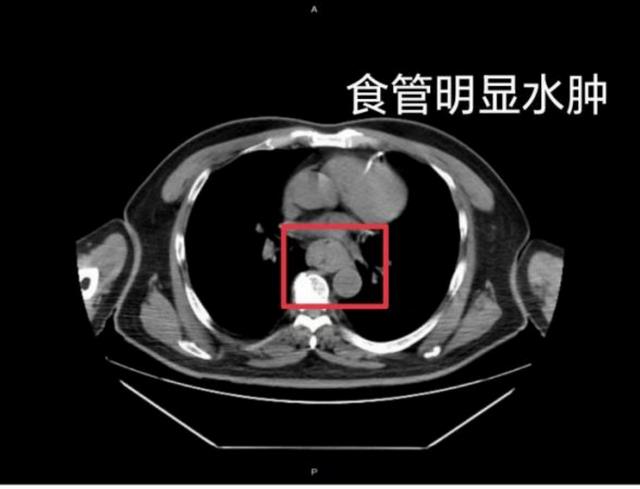

这样的情况并非个例,同样在近日,福州一位网友分享了自己因吃了一碗很烫的福鼎肉片导致呕血,并查出食管水肿的经历。

据网友回忆,“自己去厕所尝试呕吐时,直接呕出了血,一大口鲜血从嘴里喷出,总共吐了两次。”CT结果显示,他的食管全部出现水肿损伤。